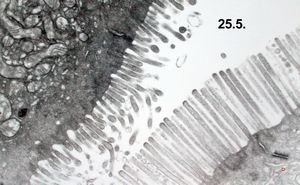

normal mucosa - jejunum - microvilli(anchored core rootlets)

normal mucosa - jejunum - microvilli

normal jejunal enterocyte

enterocyte - normal and celiacal microvilli